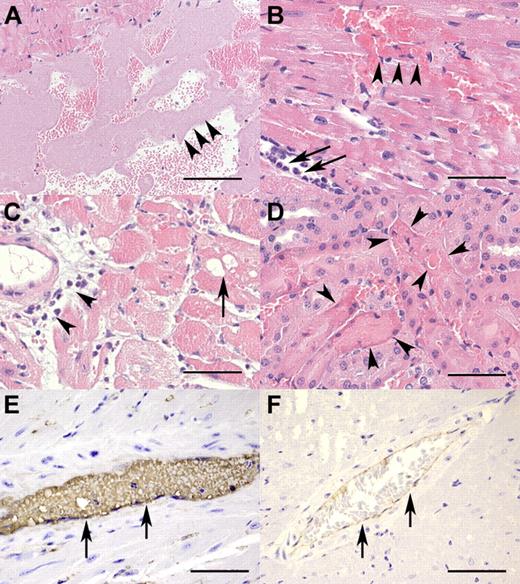

TTP-like pathohistologic changes in rhVWF-challenged animals. (A) The presence of large aggregates of platelets (arrowheads) within the left ventricle 30 minutes after TTP induction (H&E, original magnification ×100). Bar represents 200 μm. (B) Myocardial necrosis and hemorrhage (arrowheads) as well as rolling and extravasation of neutrophilic granulocytes (arrows) within the first 3 hours of TTP induction (H&E, original magnification ×400). Bar represents 50 μm. (C) Vacuolation of myocytes (arrow) and perivascular infiltration of neutrophilic granulocytes (arrowheads) within 24 hours after TTP induction (H&E, original magnification ×200). Bar represents 100 μm. (D) Renal tubular necrosis (arrowheads) characterized by loss of cellular detail, increased eosinophilia of cytoplasm, and karyopyknosis within 24 hours after TTP induction (H&E, original magnification ×400). Bar represents 50 μm. (E) Myocardial artery (arrows) immunohistochemically strongly positive for VWF 60 minutes after TTP induction (VWF immunohistochemistry, original magnification ×600). Bar represents 33 μm. (F) Myocardial artery (arrows) of an untreated control animal with minor background staining for VWF resulting from cross-reactivity of the antibody with endogenous murine VWF (VWF immunohistochemistry, original magnification ×200). Bar represents 100 μm.

These hematologic findings were consistent with pathologic findings. Macroscopic lesions were seen as early as 6 hours after rhVWF treatment and were again restricted to acute myocardial hemorrhage and necrosis. Histopathologic changes included ventricular and vascular platelet aggregations (hyaline [micro-] thrombi) in animals killed between 15 minutes and 3 hours after rhVWF administration (Figure 2A). Furthermore, myocardial lesions were recorded as early as 15 minutes after administration of rhVWF and consisted of necrosis of individual myocytes and hemorrhage. After 3 hours, infiltration of neutrophilic granulocytes along with hemorrhage of increased severity became evident (Figure 2B). Minimal, peracute tubular necrosis in the kidneys was seen 1 hour after treatment in a few animals. However, after 9 hours, lesions were observed in the majority of animals in the rhVWF-treatment group (data not shown). Immunohistochemistry revealed intense VWF staining of hemorrhagic and necrotic areas in the myocardium as well as more intense intravascular staining at all time points within the first 9 hours (Figure 2E), whereas nontreated animals showed only minimal staining (Figure 2F).